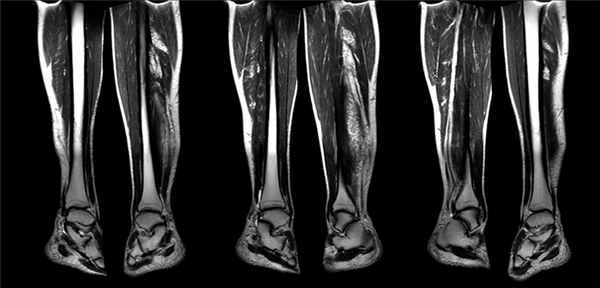

Более 20 лет при нервно-мышечных заболеваниях в клинической практике используется МРТ скелетных мышц. Данный метод дает объективную информацию о локализации и распространенности, симметричности патологического процесса, а также выявляет гипо- или гипертрофии различных мышц или мышечных групп. С помощью МРТ возможно более точно оценить избирательность поражения отдельных мышц в составе мышечных групп, которая не всегда выявляется при клиническом неврологическом обследовании. МРТ мышц — неинвазивный диагностический метод, позволяющий четко разграничить анатомические структуры исследуемой области: можно выделить отдельные мышцы, сосудисто-нервные пучки, подкожно-жировую клетчатку, фасции, кости. Кроме анатомических характеристик, МРТ позволяет оценить некоторые патофизиологические нарушения, в частности дегенеративные изменения, жировое замещение мышцы, наличие отека и воспалительных изменений скелетной мускулатуры. С помощью МР-томографа во фронтальной и аксиальной ориентации срезов и использованием Т1- и Т2-импульсных последовательностей мышц бедра и голени у больных с миопатиями получают серию изображений, позволяющий оценить состояние основных анатомических структур. Наиболее часто, в диагностике мышечных заболеваний используют аксиальную ориентацию срезов. Т1 взвешенное изображение позволяет оценить структуру мышц, их размер. Режим STIR (short tau inversion recovery) – приводит подавлению сигнала от жира, что позволяет отличить отек мышцы от жирового замещения. Применения режима STIR необходимо при диагностике ИВМ, т к позволяет визуализировать типичный для этой группы болезни воспалительный мышечный отек.

Мышечный отек – это неспецифический симптом, который может выявляться при ряде состояний: миозиты (аутоиммунный, инфекционный, саркоидный), рабдомиолиз, диабетический мионекроз, сосудистое повреждение (сосудистый инсульт), травматическое повреждение, после чрезмерной физической нагрузки, ранняя стадия оссифицирующего миозита, подострая денервация и радиационная травма.

Преимуществом МРТ является большой объем анализируемых мышц, в отличие от мышечной биопсии, когда маленький по размеру биоптат берут из одной мышцы. В любом случае, при планировании выполнения биопсии мышц целесообразно провести МРТ, для более точного определения места взятия биоптата. При проведении биопсии важно, чтобы мышца имела признаки активного воспаления, но при этом с сохраненную мышечную структуру в Т1, т.к. при выраженным замещении мышцы жиром биопсия не информативна (что имеет значение в диагностике СМВ). Важно, что при подозрении на полимиозит, а МРТ следует направлять тех пациентов, у которых проведено ЭМГ исследование, и подтвержден первично-мышечный уровень поражения, т к при развитии денервации при МРТ может выявляться отек мышц, что может привести к неверной трактовке данного феномена и диагностическим ошибкам. Для оценки состояния мышц чаще всего проводится исследование мышц бедер и голеней, но имеется методика выполнения МРТ всего тела. Так, Huang и соавт. провели МРТ всего тела у 129 пациентов с ПМ и ДМ и у 105 пациентов выявили воспалительный отек мышц. Кроме этого были обнаружены 38 случаев интерстициального поражения легких, 12 опухолей (в том числе 5 злокачественных) и у больных 15 – остеонекроз костей. Таким образом, МРТ всего тела позволяет, наряду с отеком мышц, выявить ряд состояний, очень важных и актуальных для пациентов с ДМ и ПМ как в плане оценки состояния, так и терапии. В практическом отношении следует учитывать, что с целью дифференциального диагноза у пациентов с мышечными дистрофиями используется, как наиболее информативная, МРТ мышц бедер и голеней, поэтому в сложных дифференциально-диагностических случаях предпочтение следует отдать именно исследованию мышц нижних конечностей (бедра и голени). Интересно, что в отличие от наследственных миопатий, у больных ДМ/ПМ при исследовании в режиме Т1 в клинически слабых мышцах патологические изменения не выявляются (в течение первых лет от начала заболевания). Исключения составляют СМВ и некротизирующая миопатия, при которых параллельно с признаками воспаления, появляется жировая дегенерация мышцы.

Для СМВ типично сочетание как воспалительных изменений (которые выявляются при исследовании в режиме STIR), так и мышечной дегенерации с замещением жировой тканью мышечной. Для СМВ, как и для наследственных миопатий, типична избирательность поражения. Наиболее пораженными мышцами при СМВ четырехглавая мышца (за исключением относительно сохранной прямой мышцы бедра) и медиальная головка икроножной мышцы. Также для СМВ типичным является асимметричность поражения – на доминирующей стороне мышцы отличаются большей сохранностью. Tasca и соавт. выполнили МРТ мышц 17 пациентам с достоверным СМВ, 2 с вероятным СМВ и 118 пациентам с другими миопатиями. Были получены результаты, выявившие особенности поражения мышц при этом заболевании, свидетельствующие о высокой информативности данного метода в диагностике СМВ. Таким образом, МРТ мышц является надежным инструментом для пациентов с подозрением на СМВ, и м б особенно полезным у пациентов с ранней стадией заболевания, когда еще отсутствуют все типичные морфологические признаки этого заболевания. Продолжается сравнение информативности МРТ и биопсии мышц. В этом плане интересные данные получены норвежскими учеными, которые проанализировали 230 пациентов с ДМ и ПМ и выявили, что у 87% пациентов с полимиозитом и 82% пациентов с дерматомиозитом имеют место изменения по результатам МРТ, тогда как достоверные морфологические признаки получены у 70% пациентов с ПМ и 70% пациентов с ДМ. Для полимиозита и дерматомиозита типичным является повышение МР- сигнала в режиме STIR, что отражает наличие воспалительного отека в них. При ДМ признаки воспаления могут выявляться в коже и подкожно-жировой клетчатке (что отражает наличие панникулита в рамках ДМ). Учитывая высокую частоту выявления патологических изменений в мышцах при МРТ обсуждается возможность включения МРТ в диагностические критерии ИВМ. Недостатком данного метода исследования при ИВМ является отсутствие патогномоничных для ПМ и ДМ изменений. Для ВМ характерно наличие мышечного отека, который выглядит как усиление сигнала в режиме STIR, однако аналогичные изменения могут выявляться при денервационных процессах, повреждении, ишемии, мионекрозе и после чрезмерных физических нагрузок.

Клинический пример №1. Полимиозит. Пациентка Ф 73 лет: Впервые консультирована ревматологом в сентябре 2014г, когда стала отмечать небольшую мышечную слабость в мышцах бедер, тогда имели место жалобы на утомляемость и общую слабость. В течение 2014г года отмечала некоторое уменьшение мышечной силы, хотя при этом активно двигалась, могла поднять внука, но изредка чувствует неустойчивость при приседании на низкое и стало труднее вставать с низкого стула. В сентябре 2013г впервые в биохимическом анализе отмечались повышение АЛТ до 87 АСТ до 80 ед (КФК не исследовано), калий, СРБ – норма, Препараты, в том числе статины не принимает. В дальнейшем АЛТ и АСТ продолжало нарастать, уровень калия в норме, незначительная ТТГ 4,45 (норма до 4). 27.08.14 КФК 4340, миоглобин 849 (норма 73), АЛТ 232, АЛТ 158, ЛДГ креатинин 88, мочевина 4,8, о. белок 67г/л, СРБ в норме, калий 4,4, онкомаркеры в норме. Общий анализ мочи – норма, в повторном анализе 240, АСТ 153, КФК 3850, ЛДГ 1362. При осмотре в сентябре 2014: нормального питания. Кожные покровы чистые, мышечная сила 10 баллов во всех группах мышц. Чувствительных нарушений нет. В легких дыхание везикулярное, хрипов нет. Тогда мышечная слабость отсутствовала, пациентка была направлена к неврологу при и ЭМГ – признаки генерализованного активного первично-мышечного процесса, проведено МРТ мышц: практически норма, минимальный отек мышц в STIR. К лету 2015г пациентка не могла встать с корточек. С ноября 2015г – значительное прогрессирование мышечной слабости в мышцах плечевого пояса и бедер, туловища, стало трудно вставать с низкого стула, причесываться, снимать одежду через голову, (КФК 9500ед). Повторно МРТ выявило значительное повышение МР сигнала от мышц бедер и голеней. Проведен онкопоиск: гастроскопия, маммография, УЗИ полости малого таза, ранее КТ органов брюшной полости – без признаков ЗНО. При осмотре: Нормального питания, походка миопатическая, со стула встает с приемами Говерса, руки выше горизонтального уровня поднимает с затруднением. Мышечная сила снижена в дельтовидых и трехглавых мышцах до 6 баллов, в подвздошно-поясничных, четырехглавых мышцах до 7 баллов, в двуглавой мышце бедра до 8 баллов, при перемене положения из горизонтального в вертикальное положение – пользуется вспомогательными приемами.

МРТ нижних конечностей